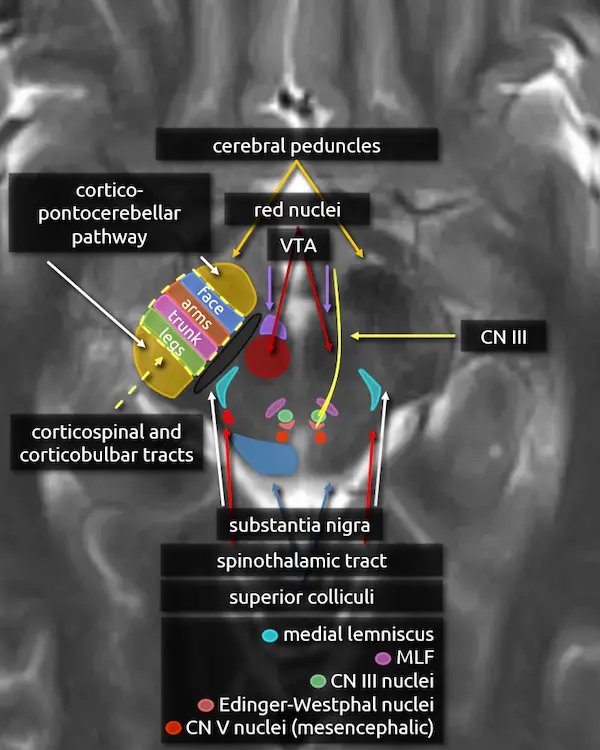

1. Cerebral peduncles

2. Superior colliculi

3. Red nucleus

4. Substantia nigra

5. Medial lemniscus

6. Medial longitudinal fasciculus (MLF)

7. Oculomotor nucleus (CN III)

8. Edinger-Westphal nucleus

9. Oculomotor nerve (CN III)

10. Mesencephalic nucleus of the trigeminal nerve (CN V)

11. Cerebral peduncles (expanded)

The corticospinal and corticobulbar tracts run through the middle third of the cerebral peduncle. Fibers are organized somatotopically; the most anteromedial part innervates the muscles of the face (corticobulbar tract) followed by the arms, trunk, and legs moving posterolateral.

The anterior and posterior thirds of the cerebral peduncle contain tracts of the corticopontocerebellar pathway. Tracts in the anterior component originate in the frontal lobe (frontopontine fibers) and tracts in the posterior component originate from the temporal lobe (temporopontine fibers).

12. Spinothalamic tract

The spinothalamic tract is responsible for pain and temperature sensation. It is found throughout the dorsal brainstem adjacent to the medial lemniscus. Like the medial lemniscus, fibers terminate at the thalamic ventral posterolateral nucleus (VPL).

Fibers of the spinothalamic tract decussate in the spinal cord, so lesions will cause contralateral loss of pain and temperature sensation.

13. Ventral tegmental area (VTA)

The ventral tegmental area (VTA) contains dopaminergic neurons that are involved in reward and goal-directed behaviors. It is found in the medial ventral midbrain in a region called the midbrain tegmentum, introduced below.

Dysfunction of the dopaminergic neurons in the VTA have been implicated in the pathophysiology of addiction, schizophrenia, and depression.